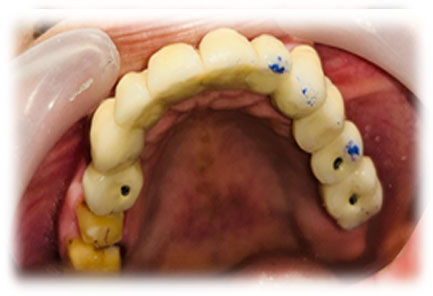

Guided Implant Surgery involves the use of advanced 3D imaging and computer-aided design (CAD) to plan the exact placement of dental implants. This meticulous planning process allows our dental specialists to visualize the patient’s oral anatomy in great detail, ensuring the implants are placed in the most ideal position for both functionality and aesthetics. The procedure is tailored to each patient's unique needs, ensuring a personalized treatment plan.

Whether you need a single tooth replacement or a full arch restoration, our Guided Implant Surgery service ensures that you receive the best possible care with minimal discomfort. Trust Pushti Dental Clinic and Pediatric Dental Center for advanced dental solutions that restore your smile and confidence.

These technique assures that the implant is precisely placed without any damage to nerves, vessels and wouldn't perforate maxillary sinus too.